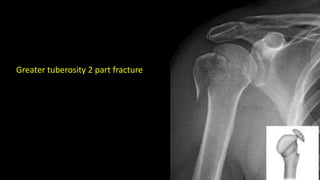

Greater tuberosity 2 part fracture

Greater tuberosity 2part fracture